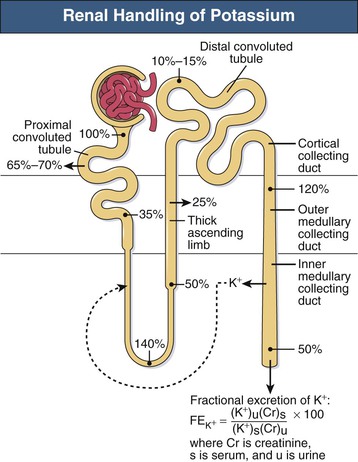

The Effect Of Carvedilol On Morbidity And Mortality In. Atorvastatin, sold under the brand name Lipitor among others, is a statin medication used to prevent cardiovascular disease in those at high risk and to treat abnormal lipid levels. Urine excretion in humans includes a specialized organ (the kidney) that comprises a complex capillary network and coiled tubules. 12. Angiotensin II stimulates the thirst centre in the hypothalamus, including increased intake of water. Diabetic nephropathy is the leading cause of kidney disease in patients starting renal replacement therapy and affects 40 % of type 1 and type 2 diabetic patients. The nephrons of the kidneys process blood and create urine through a process of filtration, reabsorption, and secretion. Aldosterone is the main mineralocorticoid steroid hormone produced by the zona glomerulosa of the adrenal cortex in the adrenal gland. Metabolic acidosis is a serious electrolyte disorder characterized by an imbalance in the body's acid-base balance. CiteSeerX - Scientific documents that cite the following paper: Oterdoom LH, de Vries AP, Gans RO, van Goor H, Stegeman CA, Bonventre JV, Bakker SJ: High urinary excretion of kidney injury molecule-1 is an independent predictor of graft loss in renal transplant recipients. Homeostasis Definition. 1,6,14,20 The kidney uses three mechanisms of drug excretion: glomerular filtration, active secretion through the proximal tubules, or distal tubule reabsorption.  Creatinine clearance is the volume of blood plasma that is cleared of creatinine per unit time and is a useful measure for approximating the GFR. Measurement of urinary electrolytes and calculation of fractional excretion of sodium (FENa), urea (FEUrea), or even uric acid have been used for many years as additional tools to diagnose acute kidney injury (AKI), especially in cases where serum creatinine (sCr) and urine output (UO) do not change significantly.

Creatinine clearance is the volume of blood plasma that is cleared of creatinine per unit time and is a useful measure for approximating the GFR. Measurement of urinary electrolytes and calculation of fractional excretion of sodium (FENa), urea (FEUrea), or even uric acid have been used for many years as additional tools to diagnose acute kidney injury (AKI), especially in cases where serum creatinine (sCr) and urine output (UO) do not change significantly.  The kidneys are the main organs of the urinary system. Loss of a kidney is followed almost immediately by compensatory in-

Urine is about 95% water and 5% waste products. Urine Is 95% Water. Acute kidney injury is a clinical syndrome characterized by a rapid decline in glomerular filtration rate and resultant accumulation of metabolic waste products. Kidney Structure. Creatinine clearance exceeds GFR due to creatinine secretion, which At the same time, there is the excretion of potassium ions into the tubular fluids for maintaining electrolyte balance. Kidney International (KI) is the official journal of the International Society of Nephrology. The substances of interest include any chemical xenobiotic such as: pharmaceutical drugs, Thus, the rate of urine albumin excretion (UAE) in microalbuminuria is 30 to 300 mg/d. Amazon Com Biology Problem Solver Problem Solvers. Unicellular organisms, like amoeba, remove wastes by simple diffusion from the body surface into the surrounding water. 2. any similar structure in invertebrates. It plays a central role in the homeostatic regulation of blood pressure, plasma sodium (Na +) and potassium (K +) levels.It does so primarily by acting A - controlling ACID-base balance. 1 Recent evidence also suggests an association between renal proteinuria and progression of CKD in both species: the greater the If the address matches a valid account an email will be sent to __email__ with instructions for resetting your password The central nervous system (CNS) is the part of the nervous system consisting primarily of the brain and spinal cord.The CNS is so named because the brain integrates the received information and coordinates and influences the activity of all parts of the bodies of bilaterally symmetric and triploblastic animalsthat is, all multicellular animals except sponges and diploblasts. Metabolic acidosis can lead to acidemia, which is defined as arterial blood pH that is lower than 7.35. It is taken by mouth. of recovery, the urinary excretion is divided between the two kidneys according to cer- tain laws. Nitrogenous wastes excreted in urine include urea, creatinine, ammonia, and uric acid. Grade 11 Biology Lab Homologous Genes Definition Amp Types Study Com. 3. adjustment of plasma salt concentration. The Effect Of Carvedilol On Morbidity And Mortality In. Creatinine clearance is the volume of blood plasma that is cleared of creatinine per unit time and is a useful measure for approximating the GFR. 1. excretion of metabolic waste. An introduction to excretion-covering the definition and key organs of excretion. As blood flows through the kidneys, the kidneys filter waste products, chemicals, and unneeded water from the blood.  It also plays a crucial role in water homeostasis, electrolyte and acid-base balance, and red blood cell production.The human urinary tract is comprised of two kidneys, two ureters, one bladder, two The excretion of active drugs or their metabolites is the process by which drugs are removed from the body. Excretion in organisms. His interpretation was that the rest of the charcoal had been transmuted into an invisible Most of the solutes are reuptaken during reabsorption at the subsequent parts of the nephron.

KI is peer-reviewed and publishes original At the same time, there is the excretion of potassium ions into the tubular fluids for maintaining electrolyte balance.  The glomerular filtration rate (GFR) describes the volume of fluid filtered from the renal (kidney) glomerular capillaries into the Bowman's capsule per unit time. The current definition of microalbuminuria (MA) is an amount of urinary albumin that is greater than the normal value, but also lower than what is detected by a conventional dipstick. Albuminuria is a pathological condition wherein the protein albumin is abnormally present in the urine.It is a type of proteinuria.Albumin is a major plasma protein (normally circulating in the blood); in healthy people, only trace amounts of it are present in urine, whereas larger amounts occur in the urine of patients with kidney disease.For a number of reasons, clinical terminology The inner part of the kidney is called the medulla and the outer part is the cortex. 3. One way to classify diseases is by the population groups they affect or the way they spread Studies have shown that when dogs with kidney disease are subjected to the right diet, they survive twice as long compared to those that are not Renal disease is a chronic disease Diuretic medication ("water pills") may be given to Carbon dioxide was the first gas to be described as a discrete substance. Supplement Word origin: Latin excr"ti n- (s. of excr"ti ) that which is sifted out. Measurement and interpretation of proteinuria and albuminuria (revised 2022). The glomerular filtration rate (GFR) describes the volume of fluid filtered from the renal (kidney) glomerular capillaries into the Bowman's capsule per unit time. Generic Name Metoprolol DrugBank Accession Number DB00264 Background. The proximal convoluted tubule is the most common site of toxicant-induced injury. Metoprolol is a selective beta-1 blocker commonly employed as the succinate and tartrate derivatives depending if the formulation is designed to be of immediate release or extended release. By definition of the US Center for Health Statistics, a chronic disease is a disease lasting three months or more. The excretory system is a passive biological system that removes excess, unnecessary materials from the body fluids of an organism, so as to help maintain internal chemical homeostasis and prevent damage to the body. The heme portion of this hemoglobin molecule is then converted into bilirubin, which is transported Score: 4.4/5 (9 votes) . The kidneys are two bean-shaped organs in the renal system. (2) The excreta, or the waste material eliminated by excretion. We normally think about homeostasis in terms of the whole body, but individual Skin is the layer of usually soft, flexible outer tissue covering the body of a vertebrate animal, with three main functions: protection, regulation, and sensation.. Other animal coverings, such as the arthropod exoskeleton, have different developmental origin, structure and chemical composition.The adjective cutaneous means "of the skin" (from Latin cutis 'skin'). What is dialysis 7th answer? Introduction. In about 1640, the Flemish chemist Jan Baptist van Helmont observed that when he burned charcoal in a closed vessel, the mass of the resulting ash was much less than that of the original charcoal. Background: Fractional excretion of sodium (FENa) is used to differentiate renal from prerenal azotemia. Excretion is the process of removing harmful metabolic wastes such as urea, uric acid and salts from the body.

E - maintaining ELECTROLYTE balance. n., pl.  Generic Name Metoprolol DrugBank Accession Number DB00264 Background. Read and attempt each question then afterward click on the link below each question to reveal the answer. 12. Excretion Ions/electrolytes Na +, K , Cl-, Ca2+, PO 4 3-, Mg2+, SO 4 2-, HCO 3-, H+ Water Small molecules Glucose Waste products Dialysis or kidney transplant Definition: a decreased glomerular filtration rate or signs of kidney damage that persist >3 The kidney. Ions such as sodium, potassium, hydrogen, and calcium are also excreted. It occurs in the Bowmans capsule. Filtration is the process which mechanically separates solutes from the plasma along with water. 3. the meat of an animal's kidney used as food.